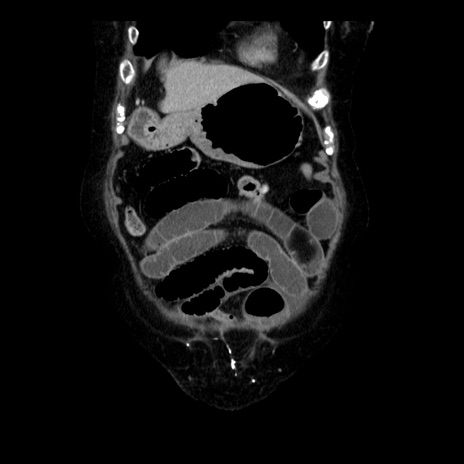

症例14(冠状断像)

【症例】 90歳代女性

【主訴】 腹痛・嘔吐

【現病歴】今朝から左側腹部痛を認めた。 経過観察していたが、嘔吐を認めたため来院。

【既往歴】 子宮癌術後

【身体所見】 意識清明、BP 127/54mmHg、P 98bpm Sp02 95%(RA)、BT 35.8°C、腹部平坦・軟腸ぜん動音聴取良好、右下腹部圧痛(+) 反跳痛なし

【データ】WBC 9800、CRP 0.46